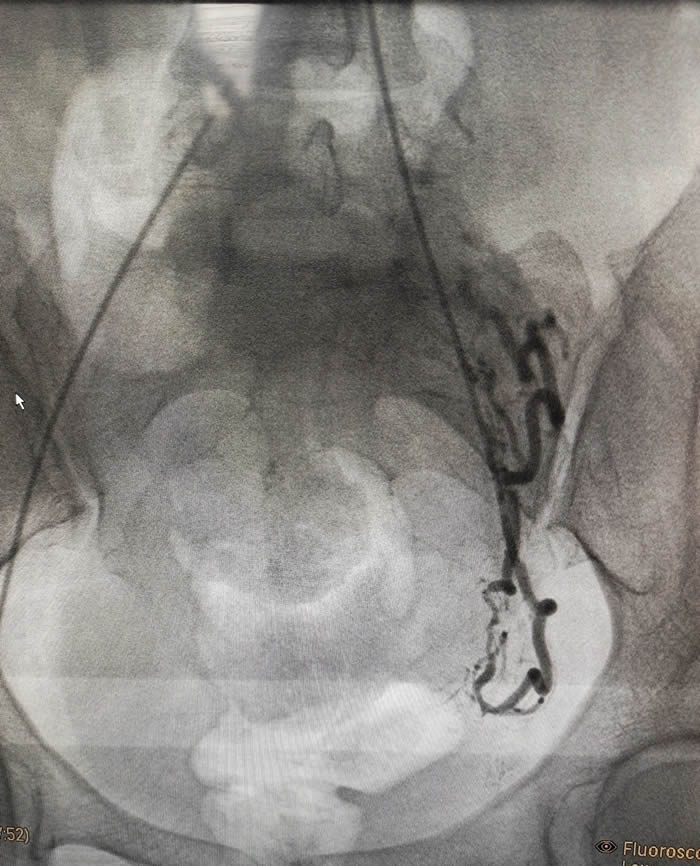

術中(zhōng)介(jiè)入(rù)科楊剛、杜長江主任(rèn)團隊率(lǜ)先行動,通過子宮動脈栓塞(sāi)術(UAE)阻斷供應(yīng)胎盤的主要血管,有效減少了術中出血的(de)風險。這種微創技術不僅創傷小,還能為後續引產和(hé)刮宮手(shǒu)術提(tí)供安全保障(zhàng)。

這場成功的救治不僅體現了徐州市婦幼保健院在高(gāo)危妊娠管理方麵的高水平,也(yě)彰顯了多學科協(xié)作的強大優勢。子宮動脈(mò)栓塞術作為一種先進的介入治療技術(shù),已被廣泛應用於前置胎盤和胎盤植入治療(liáo)中。它不僅能有效減少術中出血(xuè),還能最大限(xiàn)度地保留產婦的生(shēng)育功能。此外,藥物引產和刮宮手術的結合也為高危妊娠處理提供了新(xīn)的思(sī)路。這(zhè)種綜(zōng)合治療方案在降低手術風險(xiǎn)的同(tóng)時,減(jiǎn)小(xiǎo)了患者痛苦。